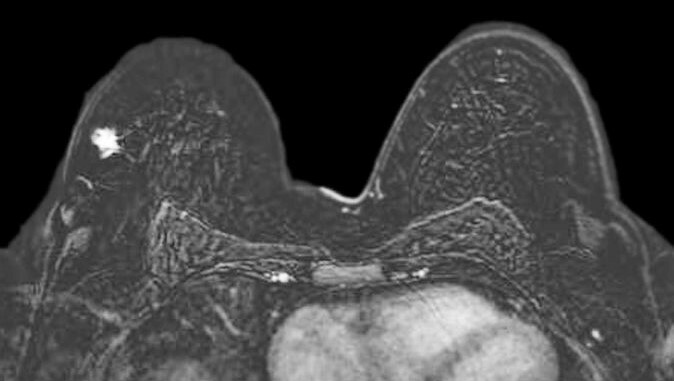

Breast MRI demonstrating breast cancer